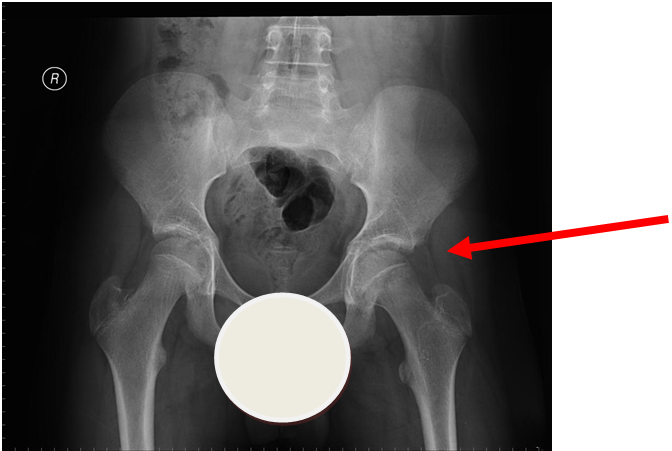

More obvious left sided SUFE (AP)

Case courtesy of Dr Gagandeep Singh, Radiopaedia.org. From the case rID: 7228

Lateral view of same patient as above

Usually occurs in late childhood / adolescence and is more common in boys than girls (2:1).  It also presents more commonly in children whose weight is above the 90th centile.  Bilateral in 25% of cases.  Onset can be acute or subacute (ie children may present with >1day h/o pain or limp).  Children may walk with an antalgic gait out-toeing, with shortening of the affected limb.  If the slip is acute, the child may be unable to walk.  Diagnosis is made radiologically and frog-lateral views are required as it may be missed on AP views.  Urgent orthopaedic opinion is required.  Unstable slips can lead to avascular necrosis of the femoral head.

Investigation

• X-ray - AP pelvis with frog lateral view (must be discussed with ortho 1st on call / ED consultant if child <8 years old)